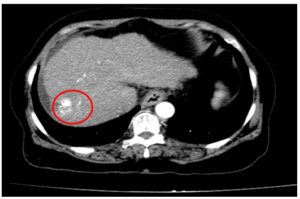

CA LÂM SÀNG: ĐIỀU TRỊ UNG THƯ PHỔI GIAI ĐOẠN MUỘN CÓ DI CĂN NÃO, TUYẾN THƯỢNG THẬN TẠI TRUNG TÂM Y HỌC HẠT NHÂN VÀ UNG BƯỚU, BỆNH VIỆN BẠCH MAI.

CA LÂM SÀNG: ĐIỀU TRỊ UNG THƯ PHỔI GIAI ĐOẠN MUỘN CÓ DI CĂN NÃO, TUYẾN THƯỢNG THẬN TẠI TRUNG TÂM Y HỌC HẠT NHÂN VÀ UNG BƯỚU, BỆNH VIỆN BẠCH MAI. GS.TS Mai Trọng Khoa(1,2), PGS.TS Phạm Cẩm Phương(1,2), BSCKII Lê Viết Nam(1), Sinh viên Lê Minh Phát(2) ...